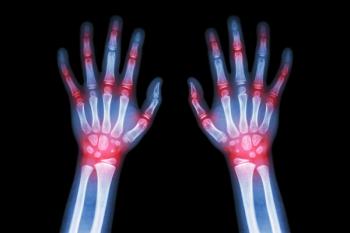

Reactive arthritis is an inflammatory joint arthritis largely characterized by joint inflammation triggered by infection. To date, no diagnostic or classification criteria have been established, but in 2014, the American College of Rheumatology issued general treatment guidelines. In this article, we highlight a new review article on treatments for reactive arthritis.

Children affected by juvenile idiopathic arthritis, manifesting as non-systemic polyarthritis, sacroilitis or enthesitis, have a number of therapeutic options available. In this article, we outline the options.